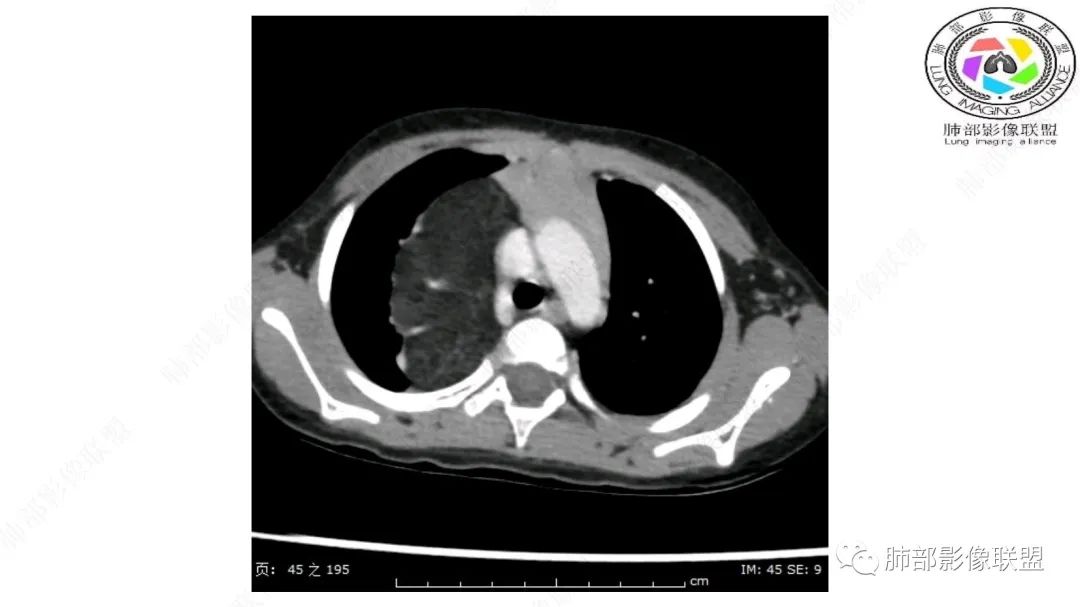

右纵隔团状,密度不均,脂肪密度为主,内可见腺体样组织,类似乳腺,病灶边缘有分叶,与胸腺关系密切,增强后血管穿行。考虑胸腺脂肪瘤(不典型垂乳征),鉴别畸胎瘤。

纵隔畸胎瘤,右前上纵隔团状脂肪密度?粘液样密度为主病变,病灶软边缘有分叶,内可见分隔,增强后血管穿行。3岁。考虑纵隔脂肪母细胞瘤,鉴别畸胎瘤。

跨肺门,包绕肺血管分支,邻近肺组织受压肺不张。

可以看到造影剂进入的丛状结构

密度不均,非纯脂肪成分。斑片状密度略高区域有轻度填充式强化。

病灶属于交界区,主体位于肺内,占位效应明显,前方突入胸壁,胸腺受压变形,胸膜显示欠清楚;病灶包绕上叶肺动脉;似乎有体动脉供血。符合肺内的点:包绕上叶肺动脉分支;符合纵隔的点:前方似乎突入胸壁,与胸腺关系比较密切,但是与上腔静脉的关系提示病灶不支持纵隔来源,前纵隔的常规会将上腔静脉受压后移、外移,这是不符合的。

2.肺动脉穿行也许是肺内来源最重要支持点!